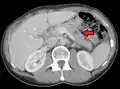

- Liver metastasis: hepatomegaly (enlarged liver), nausea[9] and jaundice[9]

This is typical route of metastasis for sarcomas, but it is also the favored route for certain types of carcinoma, such as renal cell carcinoma originating in the kidney. Because of their thinner walls, veins are more frequently invaded than are arteries, and metastasis tends to follow the pattern of venous flow. That is, hematogenous spread often follows distinct patterns depending on the location of the primary tumor. For example, colorectal cancer spreads primarily through the portal vein to the liver.